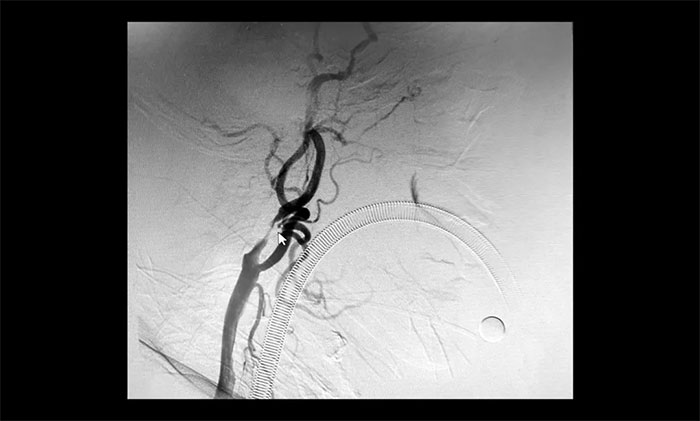

颈内动脉狭窄可分为轻度(<50%),中度(50%~69%)和重度(70%~99%),椎动脉狭窄的判别标准与之相仿。DSA检查示:患者双侧颈内动脉及左侧椎动脉存在重度狭窄,狭窄程度达到甚至超过90%,病情十分严重,遂立即收治入院。

▲ 双侧颈内动脉及左侧椎动脉重度狭窄

于耀宇主任团队针对患者病情开展审慎严谨的术前评估后一致认为,采取分期手术方式,先进行左侧颈动脉支架置入手术,待病情稳定后,再行右侧颈动脉支架置入及左侧椎动脉支架置入手术,降低手术并发症风险,从根本上解除患者因颈内动脉和椎动脉重度狭窄引起的脑缺血症状,预防缺血性脑卒中的发生和复发。

在明确告知分期手术方案,并取得患者家属同意后,5月21日,于耀宇主任和团队医生在全麻下为曹老伯先行脑血管造影术+左侧颈内动脉支架经皮置入术,术后给予预防感染、护胃、补液等对症治疗。